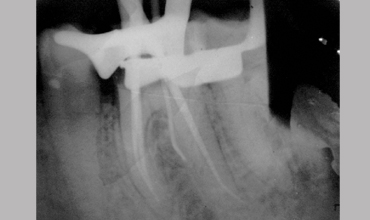

Management Of Radix

Management Of Radix Entomolaris In Mandibular First Molar